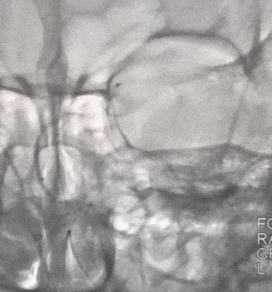

冒烟见基底动脉、双侧大脑后动脉显影较好。同轴系统缓慢跟进中间导管至V4段,支架展开后等待5分钟,缓慢整体回撤支架系统、同时负压抽吸中间导管。支架撤出体外见支架内血栓,造影见:基底动脉、双侧大脑后动脉、双侧小脑上动脉、双侧小脑后下动脉显影。

支架取出的血栓

取栓后造影

回撤6F 长鞘至左侧椎动脉V2段行3D造影,可见V3段夹层,远端血流正常,前向血流TICI分级3级。

术中完善Dyna-CT未见明显出血,导管内缓慢给予替罗非班5ml,同时静脉维持泵入替罗非班(5ml/h)。术中观察20分钟后造影见:左侧椎动脉V3段夹层较前有所改善,前向血流稳定、前向血流TICI分级3级。